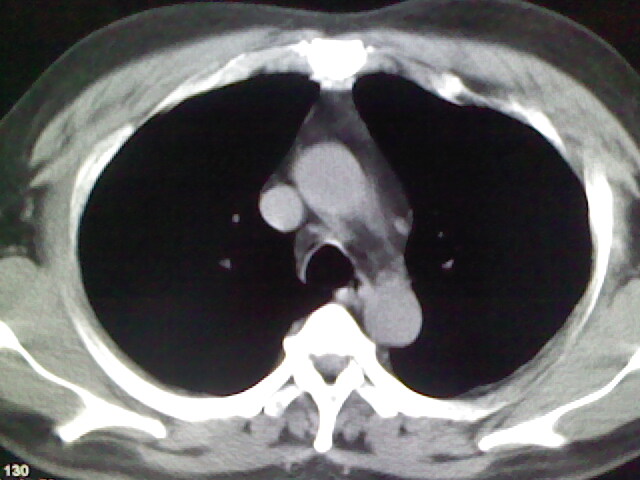

标题: CT17932:临床怀疑肺栓塞

男,34岁,自觉右侧胸痹,胸闷3天余

两肺纹理增多,余未见明确异常。

肺纹理分布较均匀,暂不提示肺梗塞